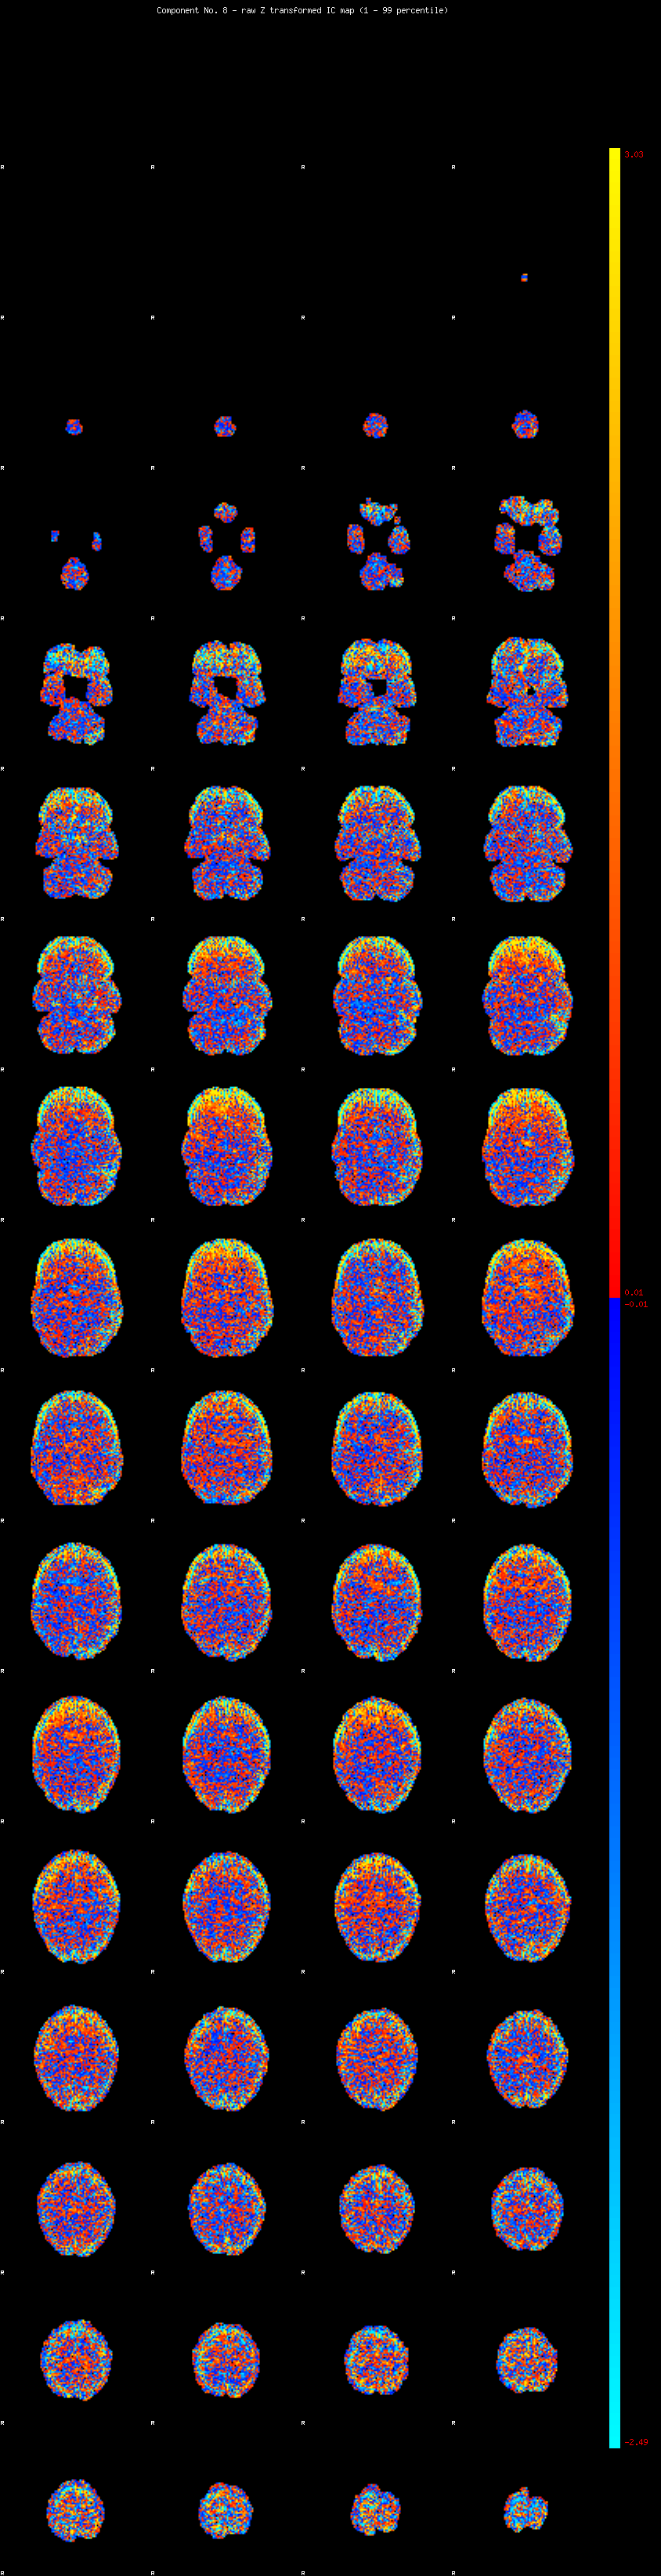

IC_8 Mixture Model fit

Means : -0.000000 3.330625 -2.902231

Vars : 1.000000 5.068361 3.431307

Prop. : 0.840049 0.091129 0.068822